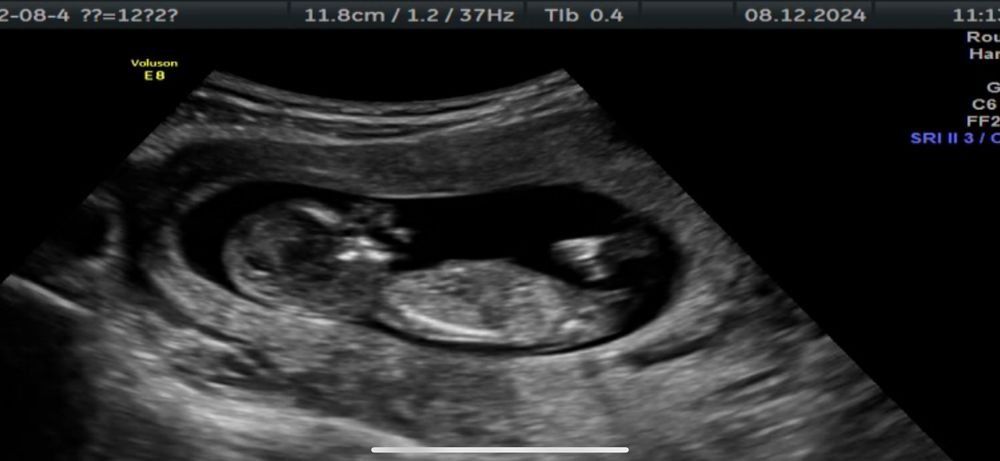

Узи 12 недель ❤️ Погадаем кто?

40 минут общения с нашей крошкой были наполнены смехом и улыбками. Спасибо вселенной за эти бесценные моменты.

У нас все хорошо, вопросов нет.

Врач сказал что может предположить пол лишь на 60%… Но так же интересно погадать 😅

Мне по половому бугорку видится девчуля… а вам?))

Но вчера пересмотрела кучу фоток и думаю что девочка 🥰